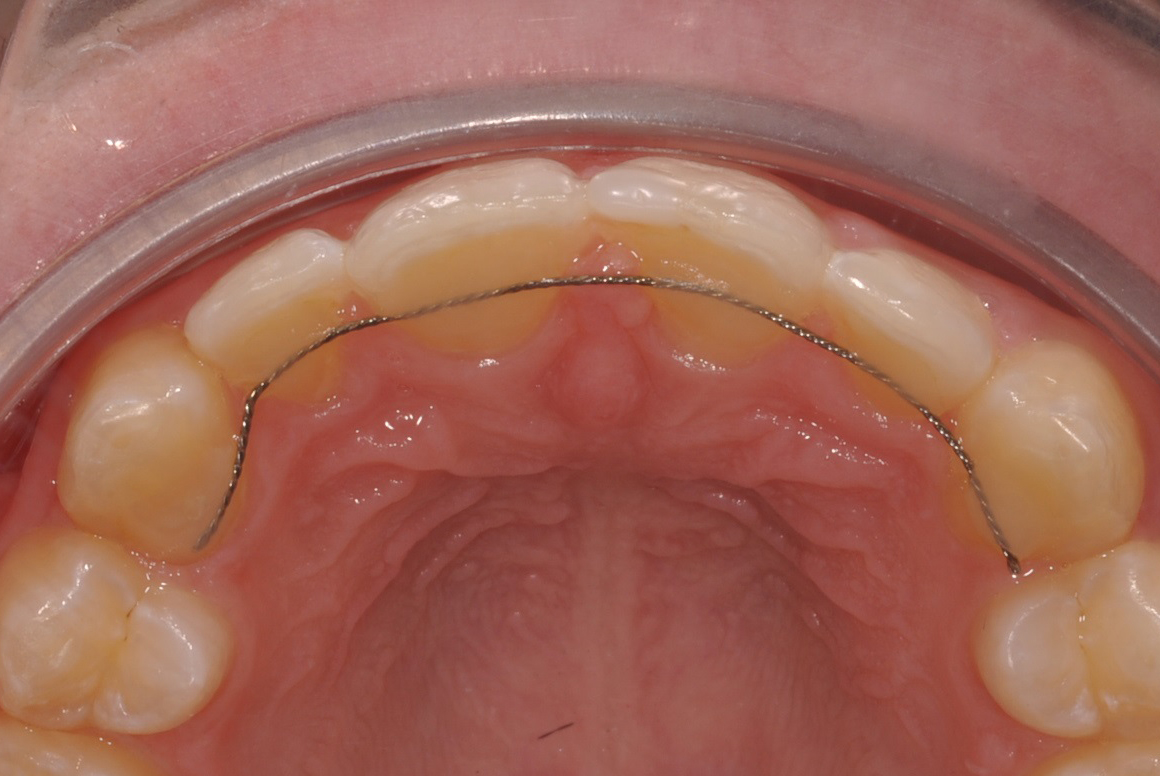

(Lingual)Retainer

Der Retainer sollte deshalb so lang wie möglich im Mund verbleiben, da eine Verschiebung der Schneidezähne ein gutes kieferorthopädisches Behandlungsergebnis funktionell und ästhetisch stark beeinträchtigen kann. Er besteht aus einem dünnen Draht, der punktförmig an den Zähnen befestigt wird.